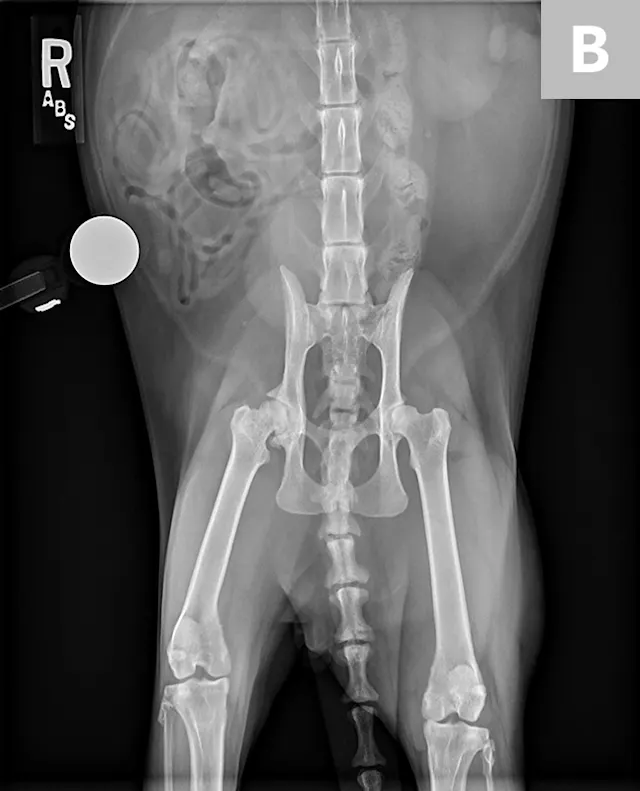

Based on clinical and radiographic findings (Figures 3-6), degenerative joint disease (DJD) involving the hips and elbows bilaterally and the right stifle, with myofascial pain in the dorsolumbar area, was diagnosed.4

FIGURE 3

Lateral (A) and dorsoventral (B) views of the pelvis. Figure A shows a moderate amount of the smoothly marginated, bridging, bony proliferations surrounding the 2nd through 5th coccygeal vertebrae. A moderate amount of kyphosis is present on the tail, centered in the bony proliferation. A mild amount of irregularly marginated bony proliferation is present surrounding the facet joint of the C5-C6 intervertebral disk space. Figure B shows poor coverage of the right femoral head by the acetabulum. A moderate amount of irregularly marginated bony proliferation is present on the cranial and caudal aspects of the acetabulum and femoral neck. There is decreased soft tissue associated with the left pelvic limb as compared with the right. A small osteophyte on the left cranial acetabulum can be noted. Image courtesy of Dr. Karen Perry. Interpretation: Chronic, healed caudal vertebral fracture, C2-C4. Moderate, right coxofemoral osteoarthritis and mild left coxofemoral osteoarthritis